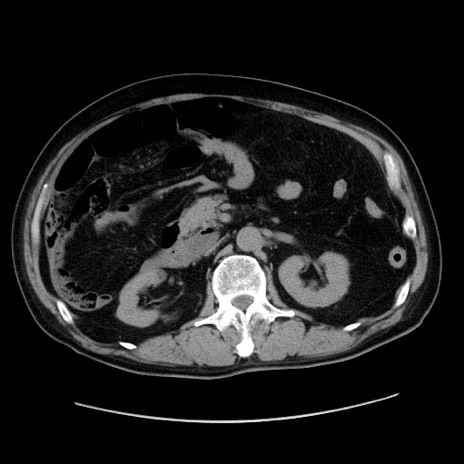

症例30(横断像)

【症例】80歳代男性

【主訴】臍周囲痛

【現病歴】約6時間前から臍下部痛が出現。次第に腹部膨隆・背部痛も生じてきたため来院。背部痛の場所は変化しない。

【身体所見】意識清明、BT 36.3℃、BP  131/87mmHg、P 87bpm、SpO2 100%(RA)、臍周囲自発痛・圧痛あり、反跳痛なし、自発痛部位に一致して板状硬あり、腹部膨隆、腸雑音減弱、CVA tenderness両側陰性。

【データ】WBC 19600、CRP 0.33